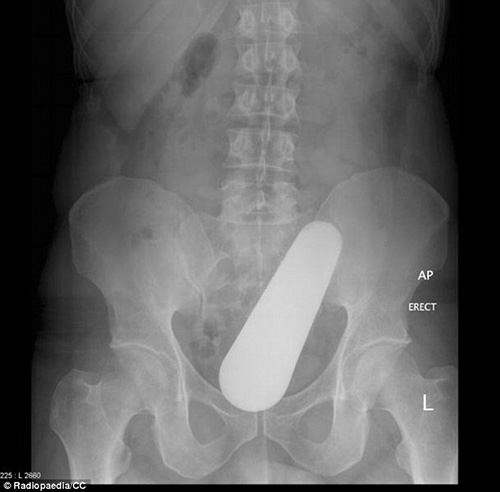

VBF- Đây là các hình ảnh được cung câp bởi các bã sĩ trong bệnh viện. Các bênh nhân sau khi để lọt các đồ vật vào người đã phải đi cấp cứu tại bệnh viện và đã được chụp X-quang để xác định đồ vật đó.Đó thường là những "vật dụng bất bình thường" được các bác sĩ khắp thế giới tìm thấy bên trong trực tràng của các bệnh nhân và chia sẻ trên trang Radiopaedia, một website giáo dục và thảo luận do các sinh viên X-quang thành lập từ năm 2005. Hình ảnh X-quang được chia sẻ trên website là vật mẫu cho việc nghiên cứu hợp tác và là giáo cụ trực quan trong giảng dạy ngành học quang quyến (môn học X-quang), hoặc dùng làm tài liệu cho các bảo tàng, đồng thời là những ví dụ giúp mọi người cảnh giác.

hiếc chày trong trực tràng người đàn ông 40 tuổi được "khổ chủ" giải thích khi nấu món ăn Malaysia đã bị trượt vào trong???